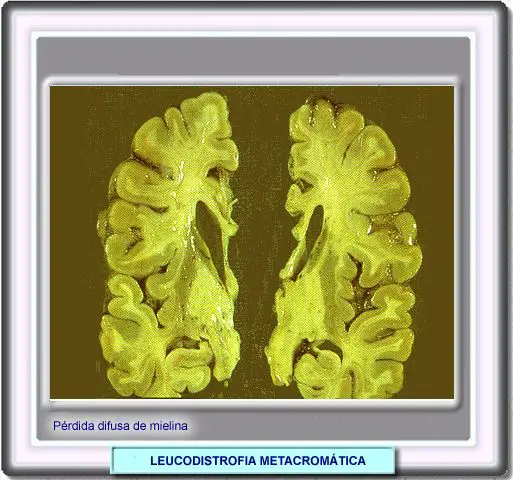

LEUCODISTROFIA METACRÓMICA

La leucodistrofia metacrómica se caracteriza por la desmielinización del sistema nervioso central y periférico.

La enfermedad es causada por una deficiencia en la enzima cerebrósido-sulfatasa que hidroliza varios sulfátidos. El gen que codifica esta enzima está situado en el cromosoma 22q13